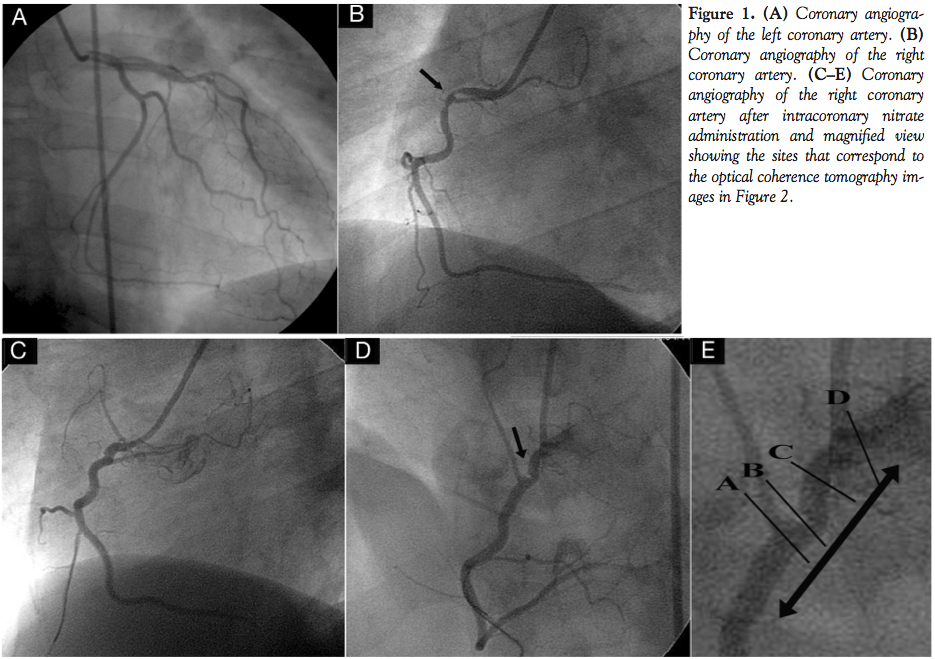

A 52-year-old male patient presented at the emergency department with progressive exertion dyspnea over the last 3 days. He had a history of smoking (70 pack years) and dyslipidemia treated with statins. T-wave inversion was evident at leads II, III, and aVF in the electrocardiogram, while cardiac biomarkers were negative. He was admitted to the coronary care unit and treated medically. Coronary angiography, performed 32 hours later, revealed an ostial lesion in the right coronary artery, while atheromatic disease was not

evident in the left coronary artery (Figures 1A and 1B). Coronary spasm was suspected and intracoronary nitrates were given to the patient leading to resolution of the spasm (Figures 1C and 1D). However, a focal luminal contrast deficit was still evident in the right anterior oblique view (arrow), raising the question of a significant lesion. In order to better assess the lesion morphology, we performed optical coherence tomography (OCT) examination of the lesion, using the non-occlusive image acquisition technique of the M3 Light Lab system and the LightLab OCT wire (LightLab Imaging, Inc), as previously described.1,2 Pullback of the OCT wire was performed in the proximal 25 mm of the artery as shown by the arrows (Figure 1E; sites A–D correspond to the panels of Figure 2). All acquired OCT images demonstrated morphology of normal vessel intima without diffuse or focal thickening (Figure 2). OCT study revealed no evidence of atheroma, thrombus, intimal disruption, or stenosis. However, vessel eccentricity was detected focally (Figure 2B), which probably led to the angiographic misinterpretation of luminal contrast deficit. Thus, despite being considered the golden standard for detection of coronary atherosclerosis, coronary angiography is subject to errors and misinterpretation in cases of extremely eccentric and tortuous lesions, in which invasive imaging techniques, such as optical coherence tomography, can minimize diagnostic errors.